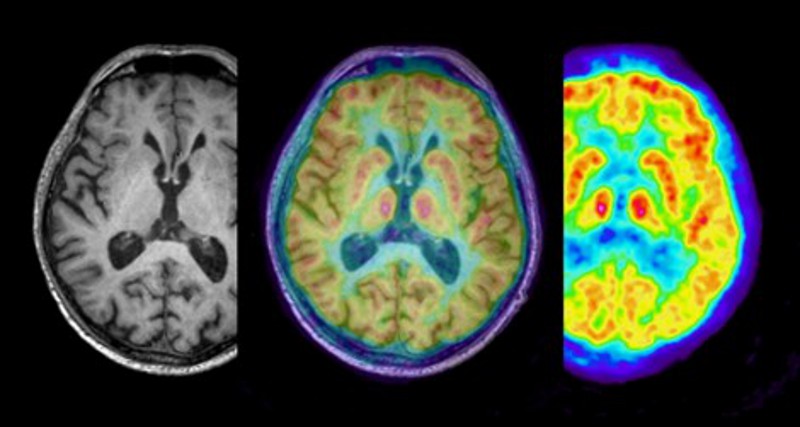

Preliminary testing has demonstrated the excellent precision of the BrainPET 7T insert, which captures brain images at an outstanding resolution of approximately 1.6 millimetres. This allows for the creation of three-dimensional brain images with 3.5 million pixels – vastly surpassing the 500,000 pixels achieved by older systems. In addition, the insert is highly sensitive, detecting over 11 percent of the gamma rays emitted by the PET tracer – a radioactive substance used to highlight metabolic activity – at the image centre. This heightened sensitivity enhances the level of detail available to scientists, providing a clearer and more accurate view of brain metabolism (the chemical processes in our brain) and overall brain function.

The BrainPET 7T insert was designed to operate within the Siemens Magnetom Terra 7T MRI scanner, which provides an ultra-high magnetic field strength of 7 Tesla, far greater than the standard MRI 1.5 or 3 Tesla scanners typically used in hospitals. The increased magnetic field strength of the ultra-high-field system provides a significantly improved signal, therefore producing sharper high-resolution images that can reveal even the finest of brain structures.